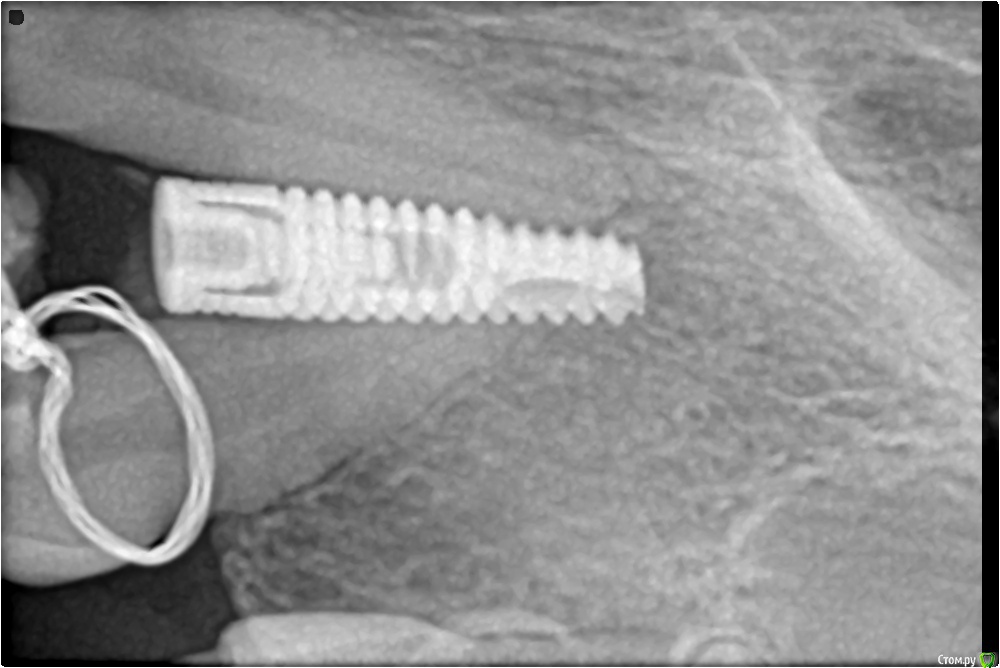

demida Опубликовано 5 мая, 2015 Поделиться Опубликовано 5 мая, 2015 хочу попросить Вас посмотреть мои снимки. У меня с детства не было двойки, клык тройку врачи перетащили скобами на место (изначально он занимал место двойки), поэтому корень зуба получился немного наклоненный. На место него мне вживили имлпант, первый раз имплант не прижился, выпал. После мне укрепили кость и вставили повторно. Но когда пришла делать снимок увидела то, что имплант близко расположен к корню. Врач сказал что причин для беспокойства нет, и что корень находится в другой плоскости и возможно просто снимок так искажает. А реакцию зуба (в частности единички) на холодное и небольшую боль при нажатие аргументирует тем, что корень и имплант близко находится друг другу. Иногда чувствую пульсирующую боль при нагрузке и небольшое покраснение хоть,но прошло 2 недели после операции. Консультировалась у другого врача, он говорит, что если бы мне задели корень зуба у меня бы была ужасная боль не только при нажатии, температура, кровотечение и т.д. Я молодая девушка и не хочу потерять еще один зуб, посоветуйте что мне нужно сделать и как понять нормально ли данные ощущения. Ссылка на комментарий

Aquarius Опубликовано 5 мая, 2015 Поделиться Опубликовано 5 мая, 2015 Необходимо сделать КТ!! 3 Ссылка на комментарий

Mane Опубликовано 5 мая, 2015 Поделиться Опубликовано 5 мая, 2015 Кт скорее всего будет фонить. Я бы сделал прицельный снимок с позиционером 2 Ссылка на комментарий